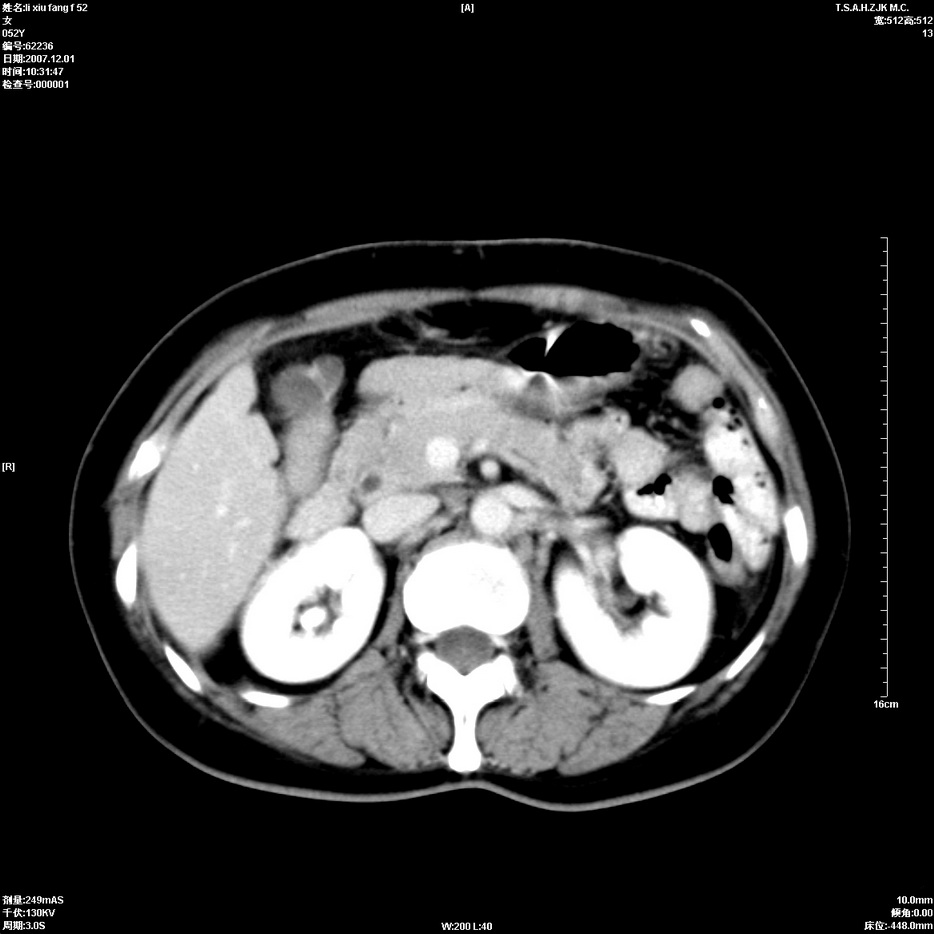

标题: CT12858:女,52岁,胎甲球蛋白861肝左叶占位,肝癌。下腔静 [打印本页]

标题: CT12858:女,52岁,胎甲球蛋白861肝左叶占位,肝癌。下腔静

肝左叶巨大低密度灶肿块,增强符合快进快出表现,有动静脉交通支;静脉期,下腔静脉内有充盈缺损,afp明显升高,支持肝癌并下腔静脉癌栓形成。

支持楼主   门静脉主干及左支癌栓形成

以下是引用拾荒者在2008-4-15 22:57:00的发言:[br]肝左叶巨大低密度灶肿块,增强符合快进快出表现,有动静脉交通支;静脉期,下腔静脉内有充盈缺损,afp明显升高,支持肝癌并下腔静脉癌栓形成。